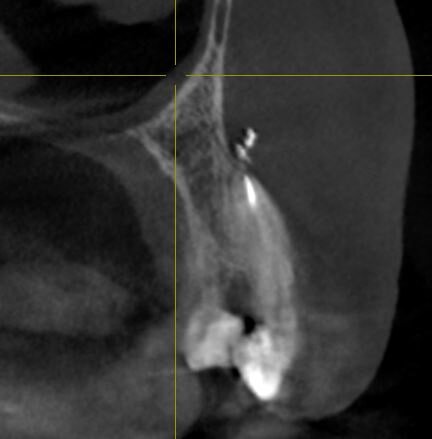

Как стоматологи могут сделать проблему в жизни, даже и не знала что может быть такое. Лечила корни верхнего клыка - обычный пульпит, удалили нерв и запломбировали каналы зубов гуттаперчей. После лечению дня 4 не отходила заморозка. Потом все как-то прошло, через некоторое время у носа образовалась опухоль. Сделали томограмму, оказывается силер или гуттаперча - пломба, чем врач набивает каналы зубов вышел за верхушку корня, и далеко, на томограмме видно что масса вышла за пределы черепа, и застряла в мягких тканях видимо. И эта масса пломбировочного материала - силер вызывает аллергию и опухоль. Верхушка корня - основание корня, его начало. Зуб не болит, не беспокоит, при нажатии ничего не болит, только лицо опухшее и несимметричное. И мой нос и так с перекошенными носовыми перегородками внутри, после того как по нему не хило долбанули, стал еще более неправильной формы (как бы это написать).

Как стоматологи могут сделать проблему в жизни, даже и не знала что может быть такое. Лечила корни верхнего клыка - обычный пульпит, удалили нерв и запломбировали каналы зубов гуттаперчей. После лечению дня 4 не отходила заморозка. Потом все как-то прошло, через некоторое время у носа образовалась опухоль. Сделали томограмму, оказывается силер или гуттаперча - пломба, чем врач набивает каналы зубов вышел за верхушку корня, и далеко, на томограмме видно что масса вышла за пределы черепа, и застряла в мягких тканях видимо. И эта масса пломбировочного материала - силер вызывает аллергию и опухоль.

Верхушка корня - основание корня, его начало. Зуб не болит, не беспокоит, при нажатии ничего не болит, только лицо опухшее и несимметричное.